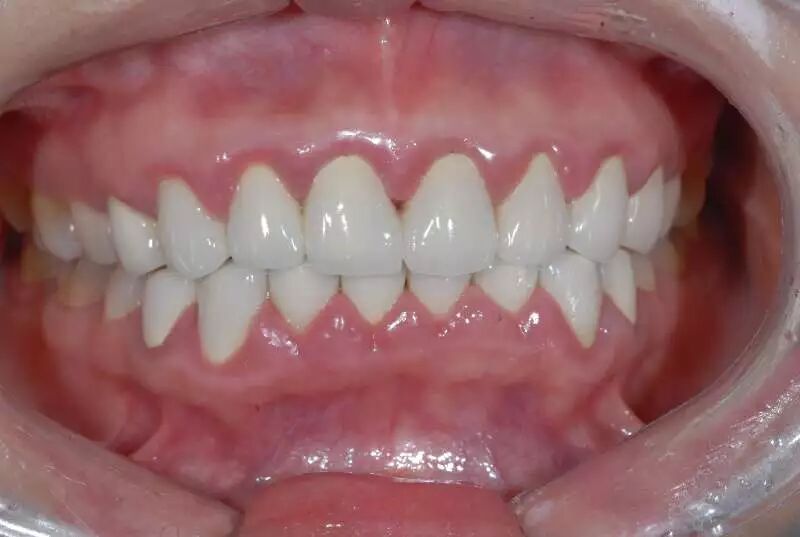

接下来再谈谈另一种不太与时俱进的烤瓷修复方式,即四环素牙和某些牙色不佳患者的全口烤瓷美容,同样的道理,十几年前因技术局限而造成相当部分患者被磨小了全口牙齿戴了烤瓷牙,以牺牲牙质的代价换取了阶段性的美观,后期乃至一辈子都在为不断出现的并发症而伤透脑筋。我们可以百度一下“明星做烤瓷牙”,百度虽说在涉及医疗的资讯上很不靠谱,但涉及明星的个人颜值信息搜索上却是相当全面。

全口牙磨小后是个什么状态,烤瓷以后又是什么效果,因人而异,但无论美观上做得多好,长期隐患如同不定时炸弹,多磨一颗牙就多一分风险。

这种全口烤瓷,以前的病例非常多,无论是公立医院还是私人诊所。但今天,微创的瓷贴面技术逐渐成熟,在理念上渐渐取代了烤瓷,可以达到磨牙量少(部分甚至完全不磨牙),对牙髓保护佳,美观自然的修复效果。